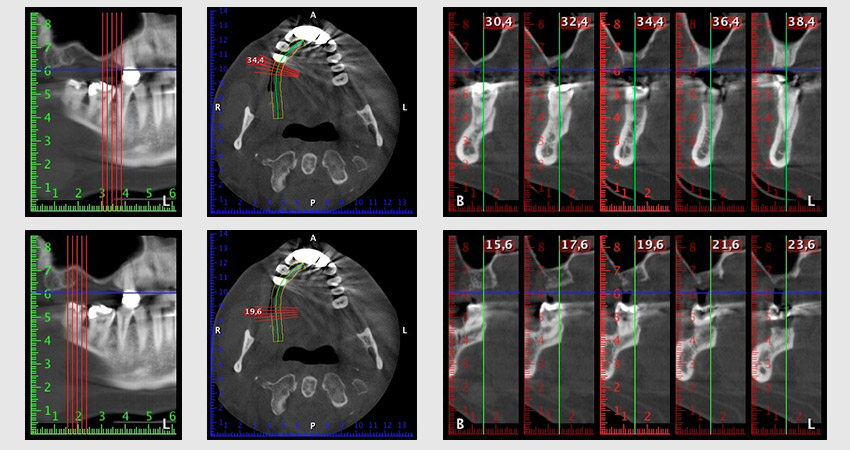

About six months after teeth 16 and 14 were extracted, a digital volume tomography (DVT, Planmeca) examination was performed for planning and risk minimization purposes. It clearly showed that the bone had not regenerated to the desired volume (Fig. 2 to 7).

Image 2 to 7: DVT with greatly reduced horizontal bone volume.